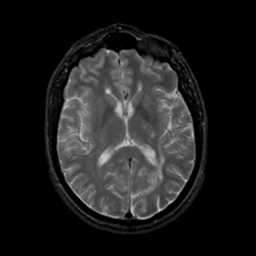

MR Study #18, July 21, 1991 -- Slice #27